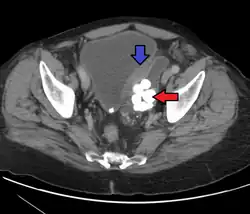

- ^ - Image by Mikael Häggström. Reference: Wojcik, EM; Kurtycz, DFI; Rosenthal, DL (2022). "We'll always have Paris The Paris System for Reporting Urinary Cytology 2022". J Am Soc Cytopathol. 11 (2): 62–66. doi:10.1016/j.jasc.2021.12.003. PMID 35094954. S2CID 246429500.